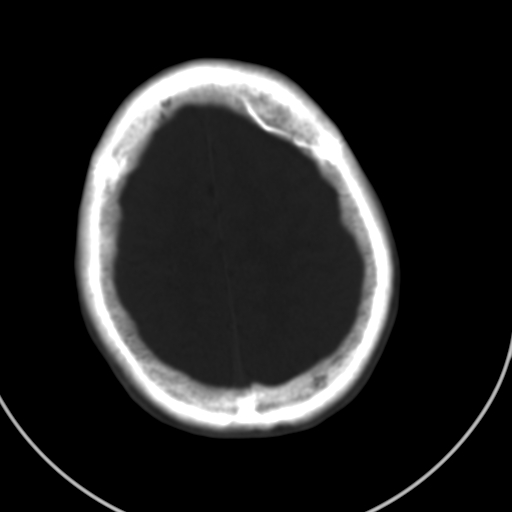

标题: CT21939:男20岁,外伤一年后,现头疼. [打印本页]

颅骨凹陷性骨折并压迫脑组织致大脑镰下疝!

是硬膜外血肿机化还是陈旧性凹陷性骨折?

硬膜外血肿机化

如果是骨折,外板正常内板这么明显凹陷,请问这样的骨折是怎样形成的?形成的机理是什么?有没有可能形成?

硬膜外血肿伴包膜钙化

左侧额部硬膜外血肿机化、骨化。